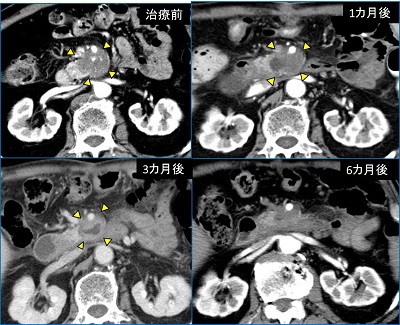

気になるナノナイフによる治療成績だが、効果としては、①ダウンステージング②長期生存を図る、という2つがあげられるという(写真5)。

「膵がんは少し大きくなっただけでも周囲の血管などに浸潤し、切除不能と診断されます。ナノナイフ治療を行うことで、腫瘍を縮小させ、中には手術に持ち込めるケースもあります」

ただ、膵がんの手術というのは、侵襲性が高く、手術ができたとしてもその後、QOL(生活の質)が落ちてしまうケースも少なくない。中には手術を希望しない人もおり、そういった場合でも、ナノナイフ治療による局所治療を行い、その後、化学療法などの全身療法を併用することで、長期生存が図れるケースがあるという。